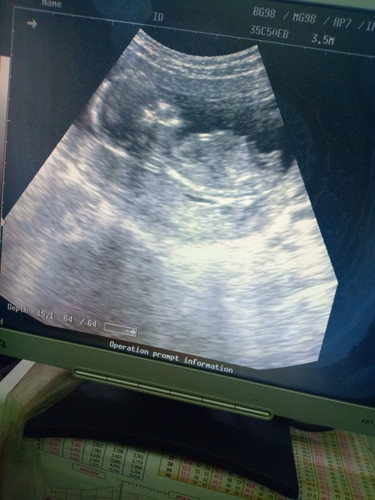

ตั้งครรภ์

คุณหมอซาวด์ให้ดูบอกน้องอาจจะมีจู๋..แม่ๆบ้านไหนอายุครรภ์ 16 w.บ้างคะ..ขอดูภาพซาวด์หน่อนคะคุณพ่อบ้านนี้อยากได้ลูกชายคะ(เรากลัวหมอแกล้งให้ดีใจ)